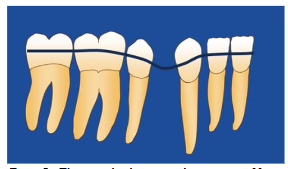

This study uses Hounsfield Unit measurements to assess bone mineral density. Bone density is one of the factors that affect tooth movement in orthodontics. The movement of the tooth through the alveolar bone is the most significant. The stance at the center of the root area makes alveolar bone density a critical factor. The bone density measurements were calculated, compared, and analyzed. The challenge of treating an extraction site is the loss of tooth structure, which disrupts the arch’s continuity. Applying force to close the gap will directly cause the neighboring teeth to tip toward the space, and a bowing effect could easily happen. This method of performing root canal treatment before extraction helps preserve the arch’s continuity for as long as possible until the tooth is ready for removal. By that time, the tooth had already been reduced interproximally to a minimal size, making the space left after extraction easy to close. This also prevents bowing and ensures proper closure of the extraction site.

The arch can be easily leveled when there is no extraction.

The arch shows a bowing effect after bicuspid extraction.

The arch continuity remains intact as the bracket can be placed on the targeted extraction tooth.

Figures 7, 8, and 9 show the differences between the non-extraction case, extraction using a straight wire without precautions when closing the extraction gap, which causes bowing, and the Root Canal Before Extraction method, which provides space even when the bicuspid has not been removed. The spaces were created using interproximal reduction. The MEAW closing loops for final alignment were activated immediately after extraction.